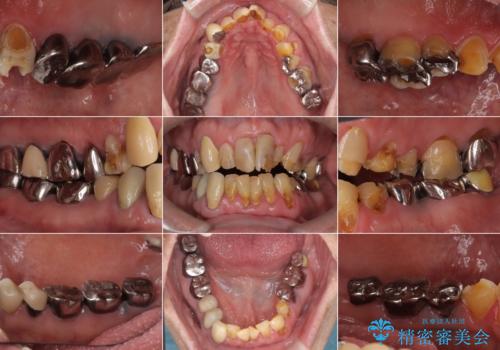

[メタルフリー] 虫歯・銀歯だらけの口腔内を全顎治療

![[メタルフリー] 虫歯・銀歯だらけの口腔内を全顎治療の症例 治療前](https://seimitsushinbi.jp/wp/wp-content/uploads/2025/03/e26a9887bc6905a2f0f51f5772b5ac9c-500x350.jpg?v=1741918285)